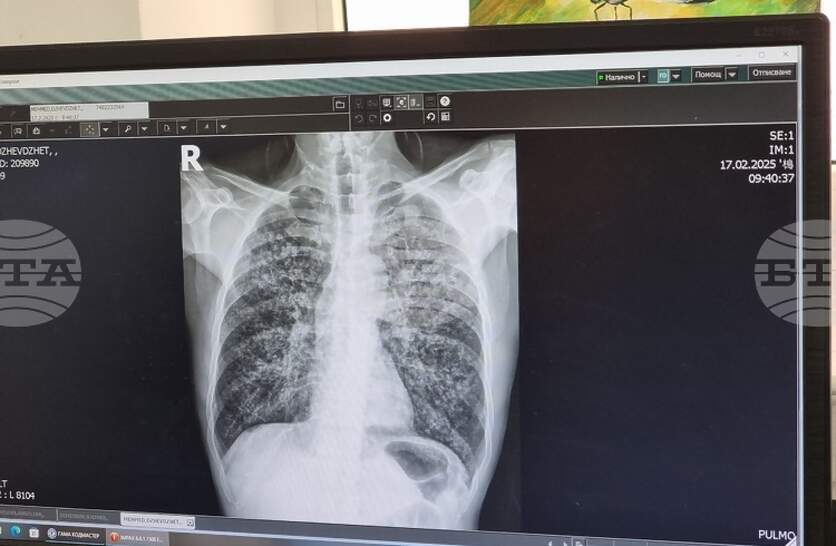

Университетската болница „Д-р Георги Странски“ в Плевен организира кампания за оценка на риска от белодробна туберкулоза, съобщиха от пресцентъра на здравното заведение. В отделението за диспансерно наблюдение на болни с пневмо-фтизиатрични заболявания ще се извършват безплатни прегледи от 23 до 27 март, всеки ден от 12:00 до 14:00 часа. Необходимо е предварително записване на място или на тел. 064/886 650 с цел по-добра организация на работата, допълват от болницата. Отделението вече се намира на нов адрес в Плевен – Втора клинична база, бул. „Владимир Вазов“ № 91. Всички процедури в рамките на кампанията са напълно безплатни за участниците, независимо от здравноосигурителния им статус. Те включват попълване на анкети, медицински прегледи и консултации със специалисти. При наличие на индикации медицинският екип ще извършва и допълнителни изследвания, като проба Манту и рентгенография на белите дробове. Кампанията за оценка на риска от белодробна туберкулоза е ежегодна. Тя се провежда четири пъти годишно – през месеците март, юни, септември и декември. В началото на месеца от болницата проведоха и кампания за безплатни прегледи с акцент върху профилактиката на бъбречни заболявания.